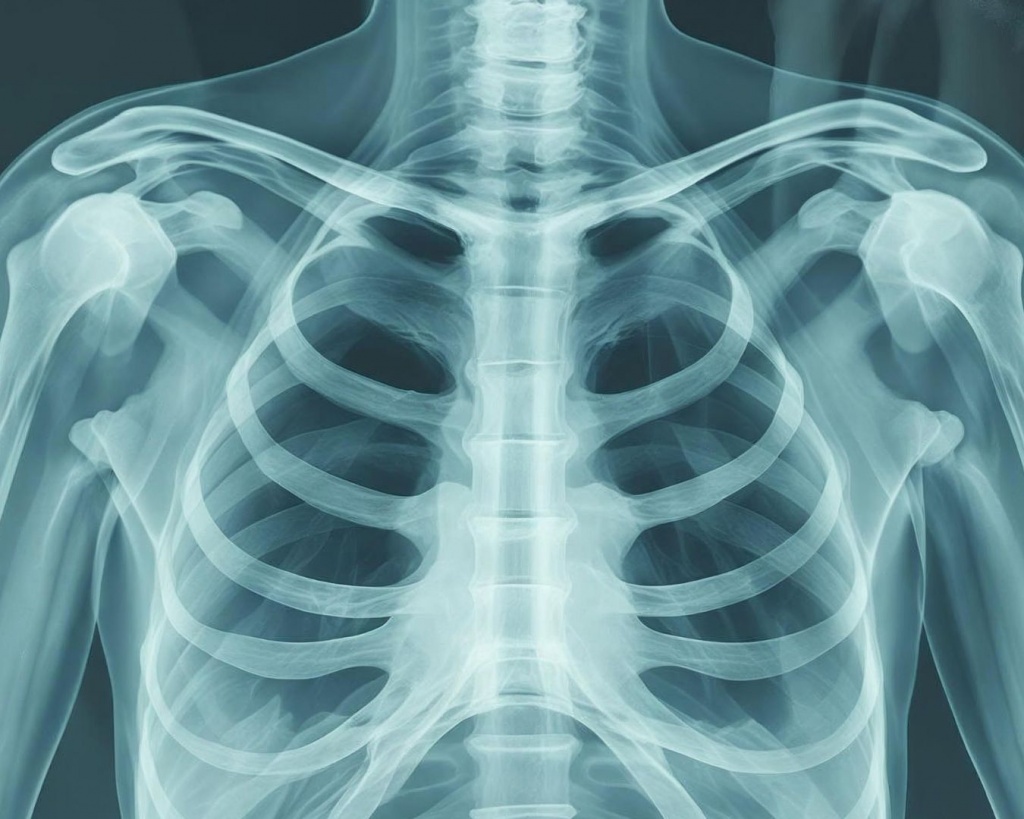

Сучасна медицина неможлива без швидкої та точної діагностики. Одним із найважливіших методів обстеження є рентгенографія. Сьогодні вона стала значно безпечнішою та інформативнішою завдяки сучасним технологіям. У клініці Medibor у Житомирі використовується цифровий рентген, який забезпечує високу якість зображення, швидкий результат та мінімальне променеве навантаження на організм.

Цифровий рентген – це сучасний метод рентгенологічної діагностики, при якому зображення одразу передається у цифровому форматі на комп’ютер. На відміну від старих плівкових апаратів, цифрова система дозволяє отримати чіткі та деталізовані знімки, що допомагає лікарю швидше та точніше встановити діагноз.

Рентгенографія допомагає лікарям оцінити стан різних органів та систем організму. Найчастіше дослідження призначають для:

діагностики травм та переломів кісток;

обстеження суглобів і хребта;

виявлення захворювань легень;

діагностики патологій грудної клітки;

Завдяки високій якості зображення лікар може побачити навіть незначні зміни у тканинах, що дозволяє розпочати лікування на ранніх стадіях.